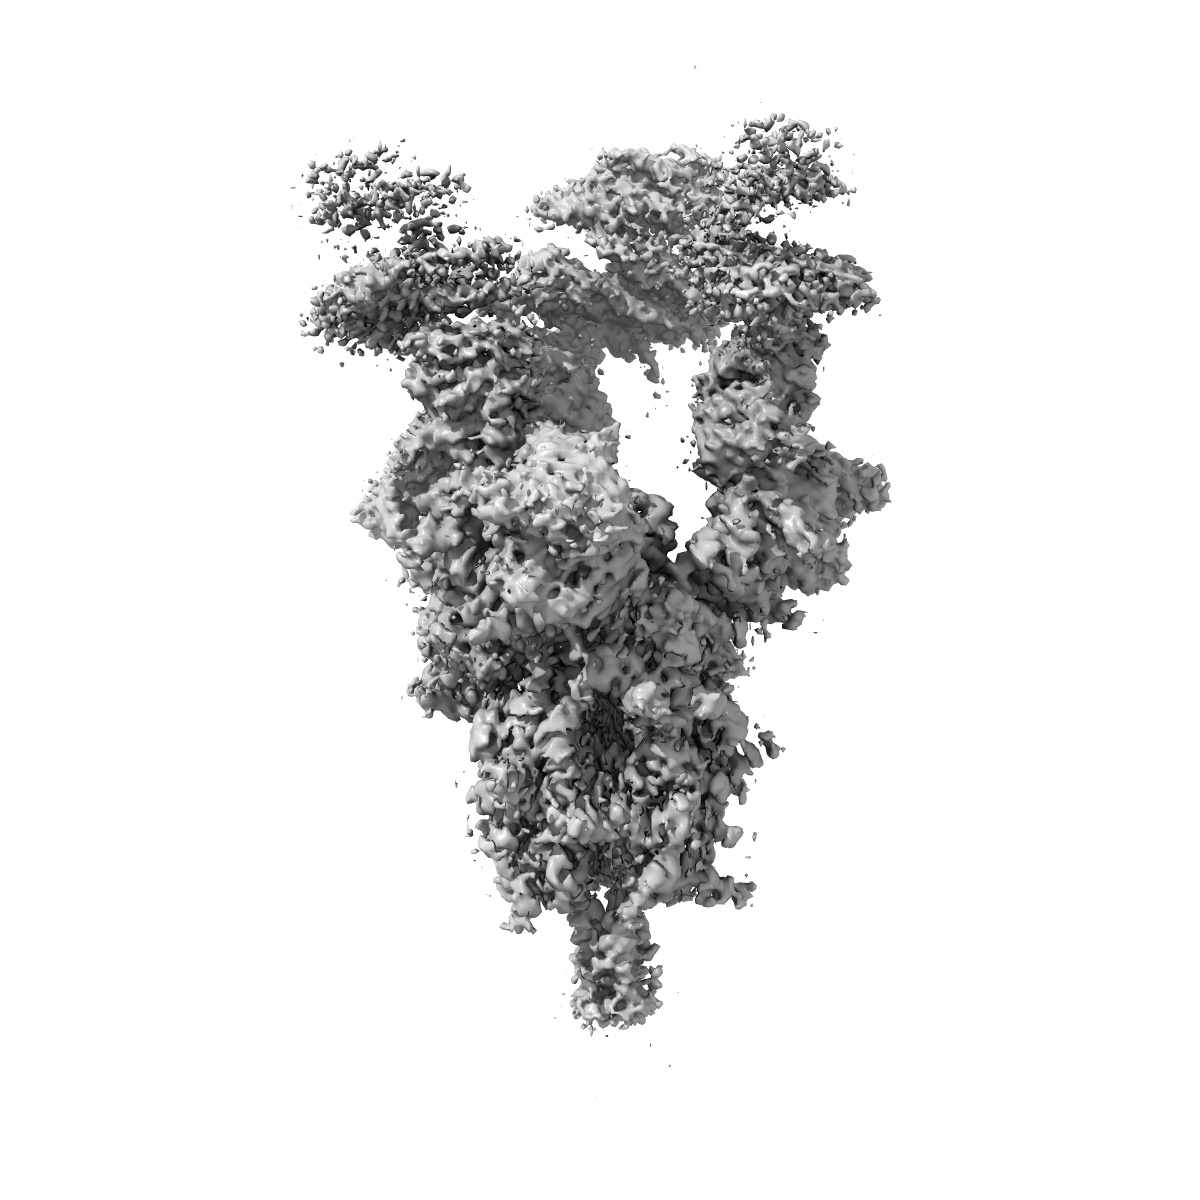

Cryo-EM structure of SARS-CoV-2 S-Kappa variant (B.1.617.1) in complex with Angiotensin-converting enzyme 2 (ACE2) ectodomain, three ACE2-bound form